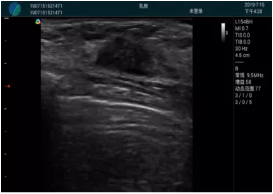

清晰顯示腺體內(nèi)低回聲快影,邊界清晰,包膜較光滑

確定進針路徑并實時監(jiān)測抽吸針與腫塊位置關(guān)系

抽吸針進入腫塊內(nèi)部進行旋切

抽吸過程中可見腫塊明顯縮小,并根據(jù)腫塊位置改變針道位置

抽吸旋切后再進行超聲復(fù)查,原腫塊區(qū)域未見殘留組織及出血

超聲引導(dǎo)下抽吸旋切取出的腫塊組織

病例二:

腺體內(nèi)部清晰顯示一低回聲塊影,形態(tài)不規(guī)則,邊界模糊,邊緣呈毛刺狀,內(nèi)部見砂礫樣鈣化

M20引導(dǎo)下穿刺活檢術(shù)

M20引導(dǎo)下平面內(nèi)穿刺取出的腫塊組織

M20查看:囊內(nèi)回聲均勻,邊界清晰,囊壁光滑

M20引導(dǎo)抽吸術(shù)后囊腫消失,原區(qū)域空腔形成,脂肪層與腺體層架構(gòu)發(fā)生改變

超聲以操作簡單、定位準確、實時顯像、費用低廉等優(yōu)勢,而成為麥默通乳腺活檢治療乳腺腫塊最常見的引導(dǎo)手段,已逐步在各大醫(yī)院開展此類手術(shù)。

2、超聲的可視化操作,能準確的顯示病灶的位置、最大徑,選擇合適的刀具,決定切口的位置和方向,避開血管、減少出血危險并實時觀察乳腺病灶的切割情況,避免造成腫塊組織殘留

可視化甲狀腺穿刺引導(dǎo)

頸動脈血流充盈飽滿,無外溢

肝內(nèi)血管顯示清晰,血流敏感無外溢

甲狀腺囊性結(jié)節(jié),囊壁鈣化,透聲好

甲狀腺囊性占位

2001年美國健康護理研究和質(zhì)量監(jiān)督局(AHRQ)批準了一項關(guān)于提高患者安全性的報告,建議:在頸內(nèi)靜脈中心置管術(shù)時使用超聲引導(dǎo)。此后超聲引導(dǎo)穿刺被用于幾乎所有的急診穿刺操作,尤其是血管穿刺。